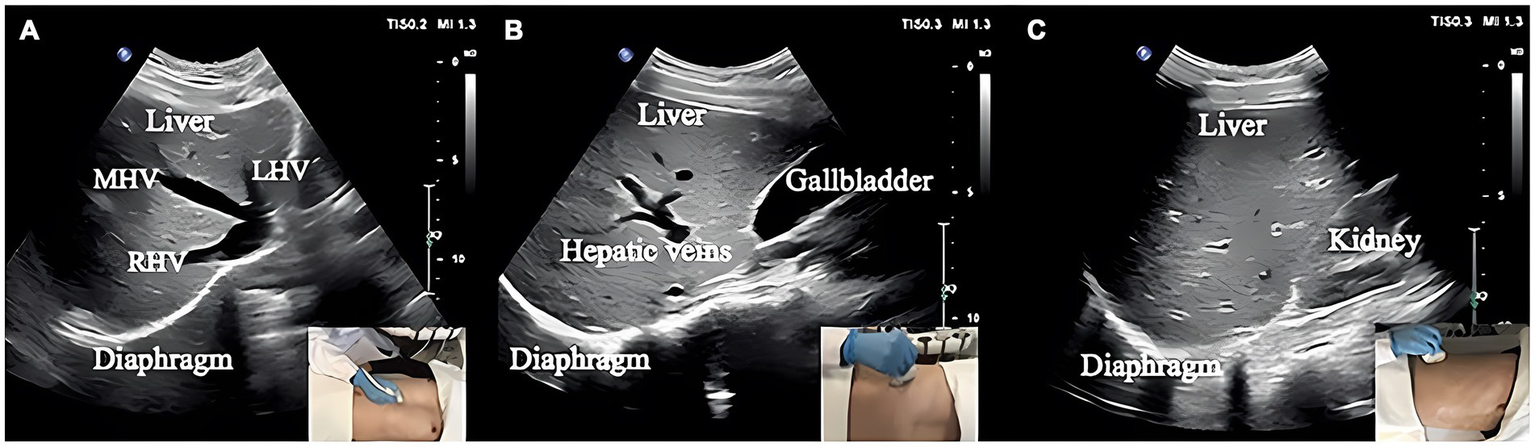

Measurements of DT and DTF require the use of a high-frequency linear ultrasound transducer (3–12 MHz). The patient should be in a semi-recumbent position, and the probe should be placed in the midaxillary line at ribs 8–10, perpendicular to the intercostal space. In B-Mode, the diaphragm can be visualized as a three-layered structure, with the upper hyperechoic layer being the pleura, the lower layer being the peritoneum, and the middle layer being the diaphragm (29) (Figures 2A,B). In contrast, DE measurements are performed using a low-frequency abdominal convex probe (3–5 MHz), the patient should be positioned at a 45-degree semi-recumbent angle, and the ultrasound probe should be placed parallel to the right costal margin at the right midclavicular line, using the transverse section of the liver as an acoustic window. Alternatively, the probe can be placed perpendicular to the costal margin to obtain a longitudinal section of the liver (Figures 2C,D). It is also possible to obtain diaphragm images at different interfaces using liver vessels as markers, however, this method is not commonly used (Figure 3). In B-Mode, the high echo shadow covering the liver surface represents the diaphragm, switching to M-Mode allows for the observation of the diaphragm waveform synchronized with the respiratory cycle (Figure 4B). On the left side, the probe is placed at the 8–10th rib along the midaxillary line, parallel to the intercostal spaces, the other methods are the same as for the right side (Figure 4A) (29). Ultimately, ultrasound is clinically reproducible (32) and has become an essential tool for most clinicians, its overall measurement failure rate has decreased from 27% a decade ago to 0.7% today, demonstrating the effectiveness of ultrasound technology (33).

Figure 3

(A) Section I: Oblique section of the lower right costal arch through the second hepatic portal with the left hepatic vein (LHV), middle hepatic vein (MHV), and right hepatic vein (RHV) as anatomical markers. (B) Section II: Oblique section of the right intercostal passage through the first hepatic portal with the inferior vena cava, hepatic vein, and gallbladder as anatomical markers. (C) Section III: Sagittal section of the liver and right kidney with the right kidney and hepatorenal space as anatomical markers (31).